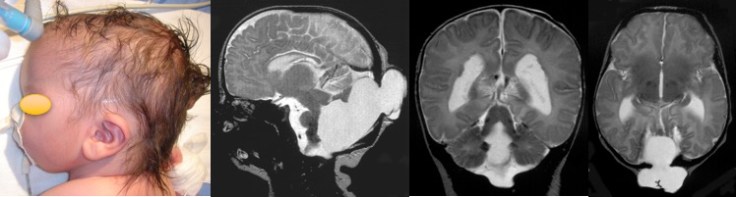

A: occipital meningocele diagnosed prenatally; B: moderate-size meningocele at birth; C: tonsillar herniation on MR at 4 months; D: increased volume of meningocele at surgery - encéphalocèle occipitale supra-tentorielle, épidermisée ou non